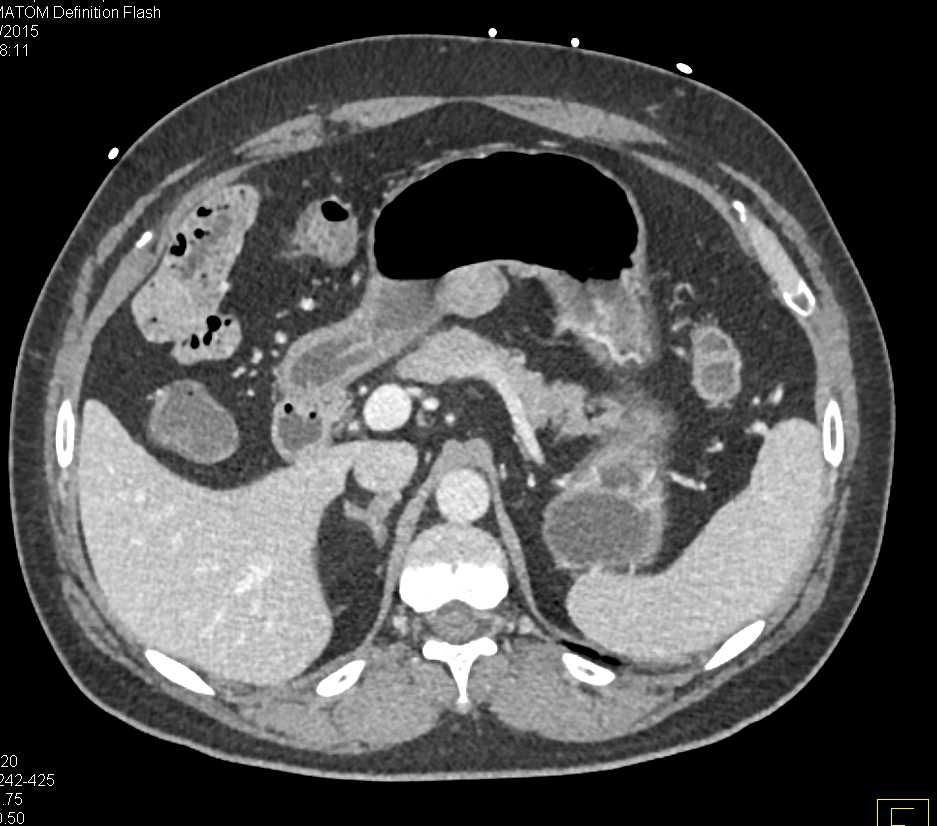

The Multidetector CT (MDCT) images of the case. (A) The outer sheath Colon White Spots It usually begins as small clumps of cells called polyps that form inside the colon. Microscopic colitis is swelling and irritation, called inflammation, of the large intestine. The intervening mucosa appeared normal (figure. Colonic pseudolipomatosis is a relatively rare incidental finding of multiple occasionally confluent white plaques containing microbubbles reported in. Colon cancer typically affects older adults, though it can. Colon White Spots.

Figure 2. Abdominal CT (coronal image) showing an enhancing mass in the Colon White Spots Colonic pseudolipomatosis is a relatively rare incidental finding of multiple occasionally confluent white plaques containing microbubbles reported in. It usually begins as small clumps of cells called polyps that form inside the colon. The intervening mucosa appeared normal (figure. Colon cancer typically affects older adults, though it can happen at any age. Elevated, whitish plaque lesions that seem to form. Colon White Spots.

Colitis Right Colon Colon Case Studies CTisus CT Scanning Colon White Spots Colonic pseudolipomatosis is a relatively rare incidental finding of multiple occasionally confluent white plaques containing microbubbles reported in. The intervening mucosa appeared normal (figure. Colon cancer typically affects older adults, though it can happen at any age. It usually begins as small clumps of cells called polyps that form inside the colon. This large intestine is also called the colon.. Colon White Spots.

Colitis Right Colon Colon Case Studies CTisus CT Scanning Colon White Spots Microscopic colitis is swelling and irritation, called inflammation, of the large intestine. Colon cancer typically affects older adults, though it can happen at any age. It usually begins as small clumps of cells called polyps that form inside the colon. The intervening mucosa appeared normal (figure. Colonic pseudolipomatosis is a relatively rare incidental finding of multiple occasionally confluent white plaques. Colon White Spots.

Colitis Right Colon Colon Case Studies CTisus CT Scanning Colon White Spots The intervening mucosa appeared normal (figure. Elevated, whitish plaque lesions that seem to form as the colonoscopy is performed have been coined as “snow white”. It usually begins as small clumps of cells called polyps that form inside the colon. This large intestine is also called the colon. Colonic pseudolipomatosis is a relatively rare incidental finding of multiple occasionally confluent. Colon White Spots.